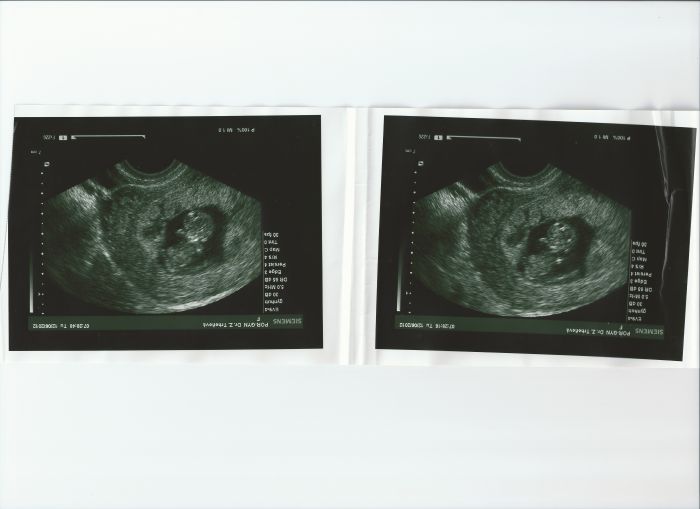

Tady přikládám poslední fotku z utz bylo to tuším na 12tém týdnu, uř se těším ted 27. a 28. snad bude vše v pořádku bojim bojim